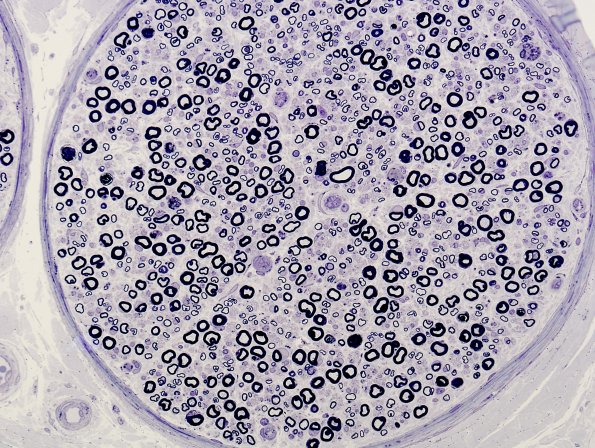

These images of the sural nerve show loss of large and small myelinated axons, probably large>small, and multiple fascicles with some variation in axon density. (plastic section)